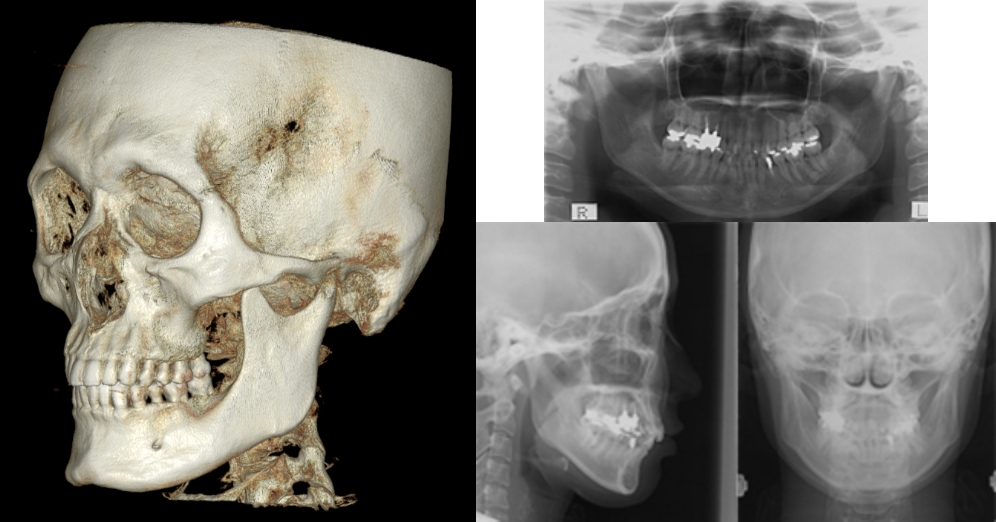

精密検査と“骨に調和する”

治療計画

セファロ(頭部X線)分析・3DCT・模型(スキャン)分析を行い、

• 上下顎の骨格バランス

• 歯の角度・上下前後の位置

• 歯列弓の幅・歯ぐきの厚み

• 口元(口唇)の見え方

を総合評価。前歯・奥歯をどこへどれだけ動かすかを設計し、IPR(歯と歯の間をわずかに整える処置)や抜歯の要否、親知らずの扱いまで丁寧に判断します。

レントゲン撮影

模型分析

レントゲン分析

口元のシミュレーション

まず、セファロ・3DCT(あごの骨や歯の根の情報)・口腔内スキャン(歯の形とかみ合わせの情報)をとり、これらを重ね合わせて1本ずつ歯をデジタル上で並べ直すシミュレーションを作成します。

3DCTの治療例